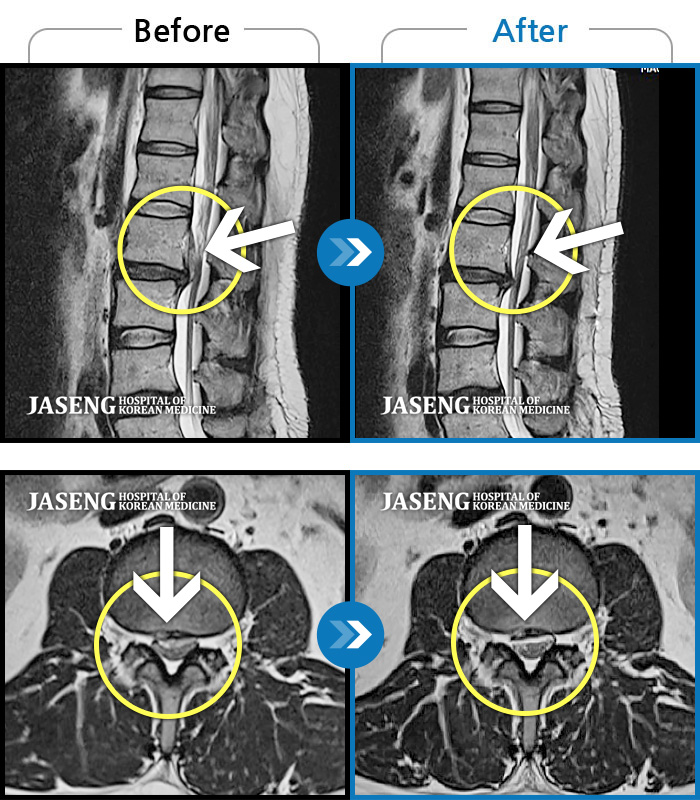

ȯںп  Ǹ   ǿ ԿǾ, ο  ġ  ۿ     Ƿ   ġḦ Ͻñ ٶϴ.